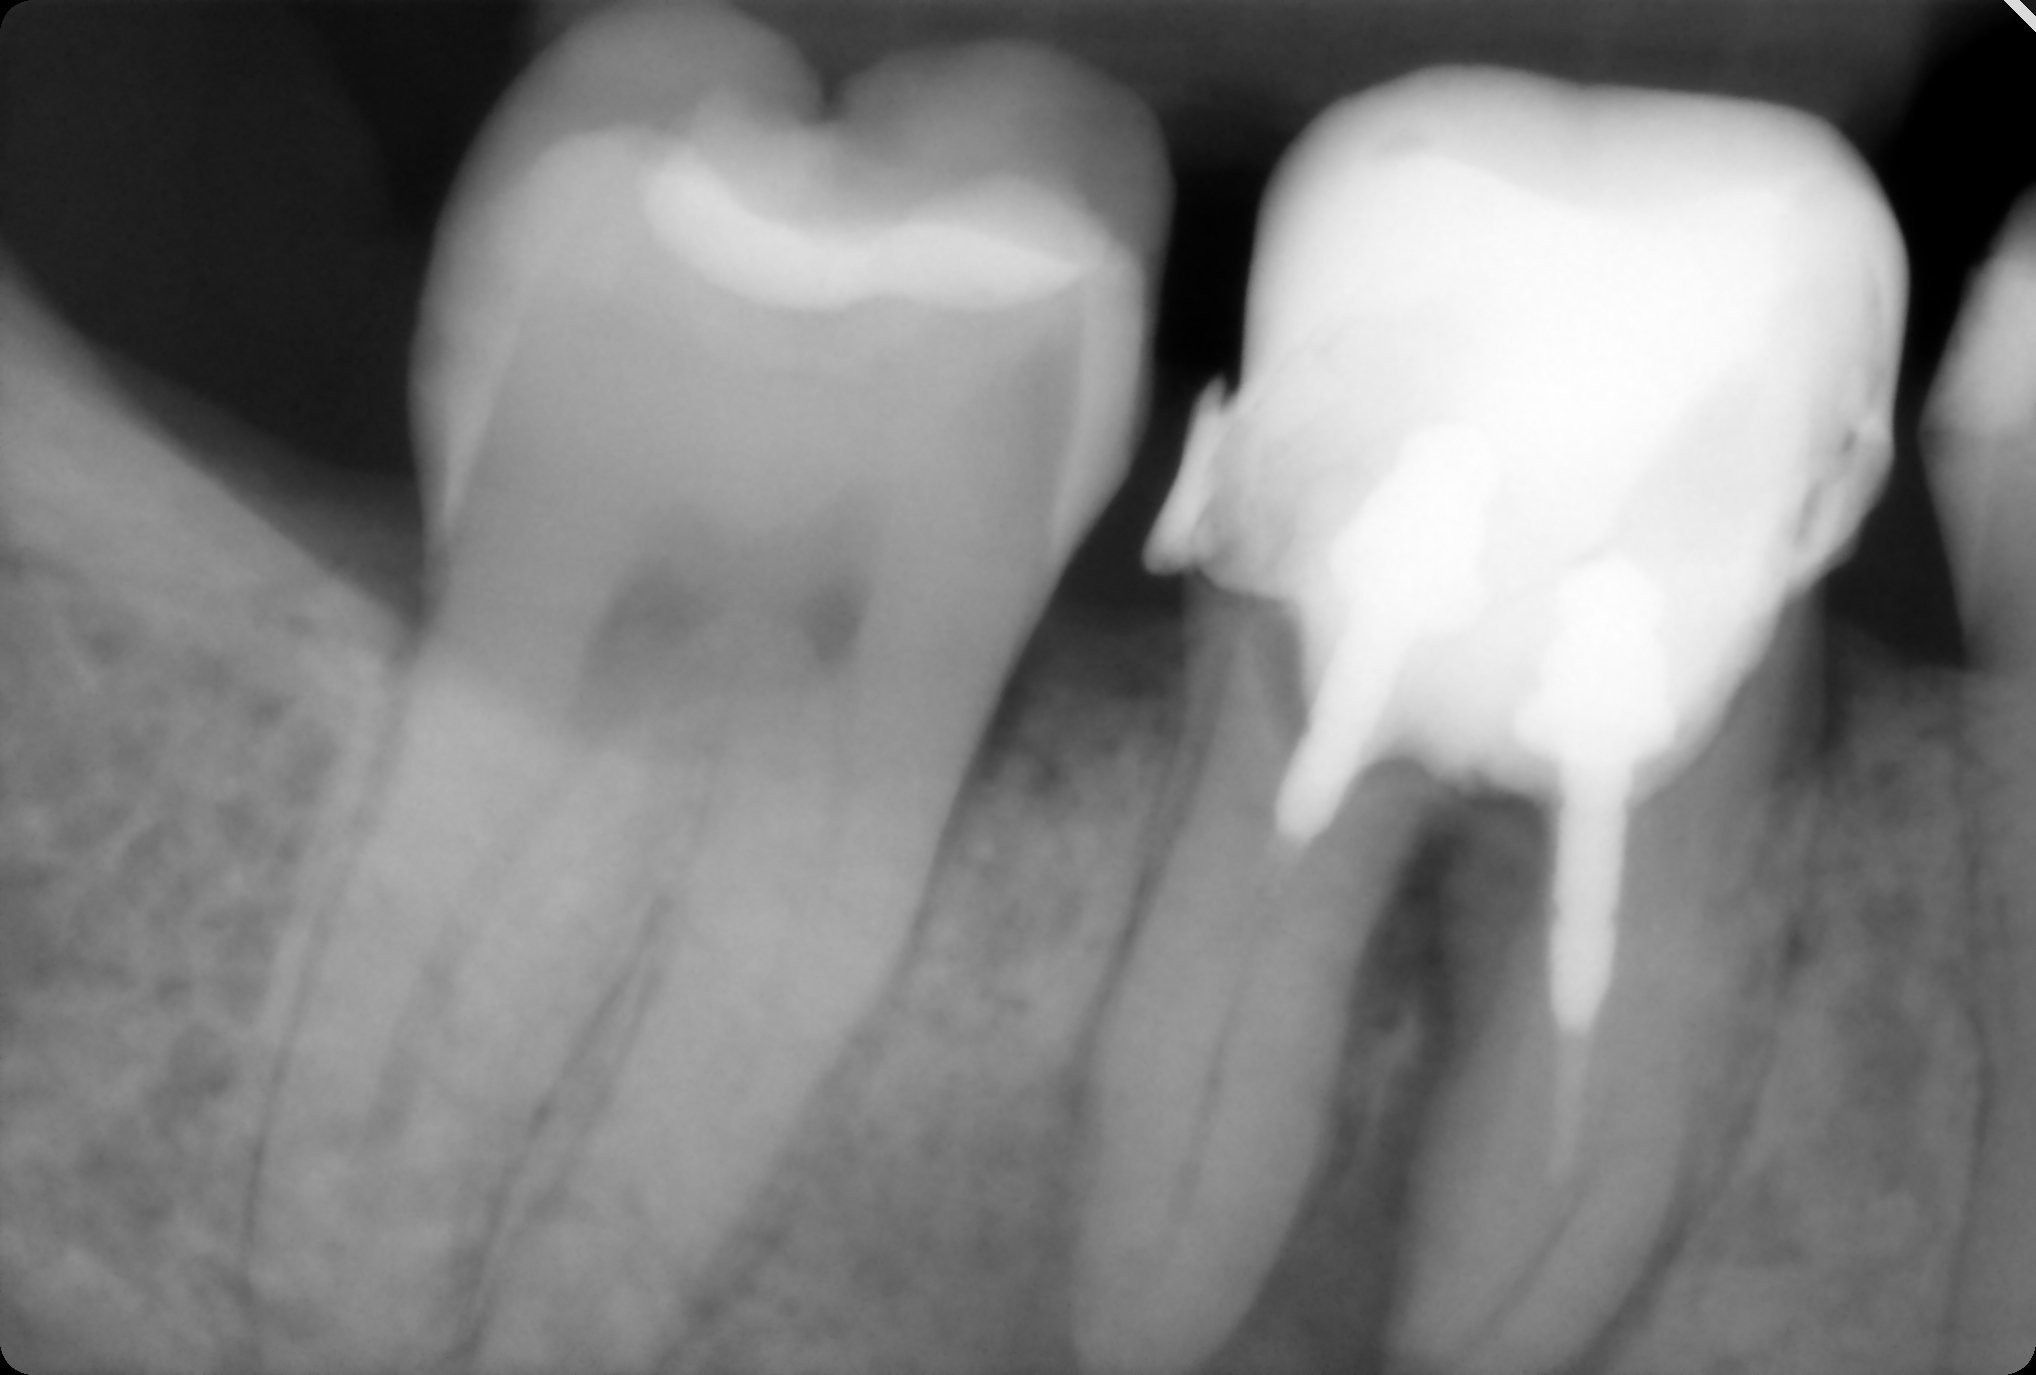

Здравейте, появи ми се гнойна торбичка на умъртвен зъб. Искам да попитам има ли нещо притеснително  на снимката?Според зъболекаря разтоянието между корените се дължало на някакъв дефект.  🤔🤔

nelicka, зъбът има обширно възпаление (по-тъмната част, която съм посочила със стрелка), която може да се дължи на лошото лечение на кореновите канали, а също и на изтънялото “дъно” на зъба, оградила съм с кръг, пломбата изглежда много дълбока и е възможно да има перфорация, ще се прецени най-добре, ако се свали цялата пломба и се огледа хубаво зъбът.